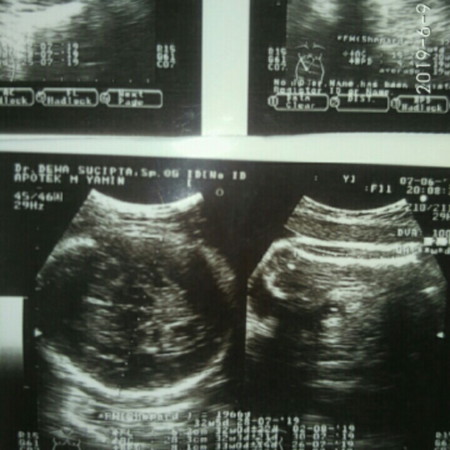

hasil usg

Bun ada yg bisa jelasin hasil usg ini gk?? Sy penasaran sm tulisan nya,tpi sy gk paham ? ada yg bisa bantu?? Kira²berat badan janin nya brpa ya.. Dan hpl kta dokternya akhir juli,padahal kan 18 juli ? +FL : 6,2cm +AC : 28,3cm +BPD : 8,1cm